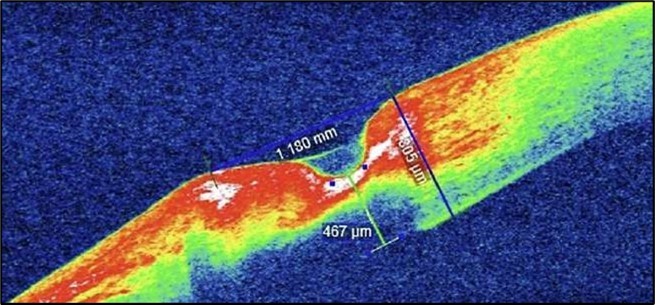

Despite systemic and topical management over one month, the epithelial defect persisted, indicating refractoriness to medical therapy. OCT imaging showed ulcer depth reduction to nearly 42% stromal thinning and width of 1180 µm, highlighting partial corneal healing. In view of the persistent ulcer and ongoing local inflammation, a conjunctival resection was performed to excise the perilimbal inflammatory focus and promote corneal repair Figure 3a and 3b.

Serial anterior segment OCT was employed throughout treatment to monitor corneal changes and response to interventions. Figure 7a, Figure 7b, Figure 7c, Figure 7d illustrate the ulcer’s progression: initial severity, minimal early response to medical therapy, post-operative healing after conjunctival resection, and sustained recovery at six-month follow-up.

Figure 7b.(Following systemic immunosuppression): AS-OCT shows a reduction in ulcer depth to 338 µm and a narrower ulcer width of 1180 µm, suggesting minimal therapeutic response. The ulcer bed remains irregular with persistent stromal hyperreflectivity, likely due to ongoing inflammation. The overhanging edge is less prominent, and partial re-epithelialization is observed.

In our patient, 42% stromal thinning (1180 µm), without descemetocele or perforation did not warrant these more invasive procedures.